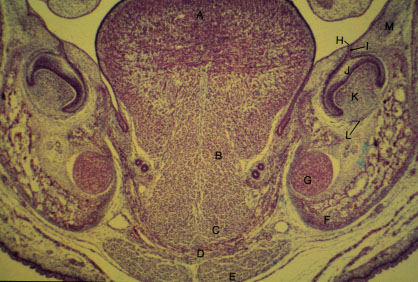

- K-slide 5: Higher magnification

- A. Tongue

- B. [Genioglossus]

- C. [Geniohyoid]

- D. [Mylohyoid]

- E. [Anterior belly of digastric]

- F. Developing mandibular bone

- G. Meckel's cartilage

- H. Dental lamina

- I. Deciduous dental lamina

- J. Enamel organ

- K. Dental papilla

- L. Dental follicle

- M. Mandibular vestibular lamina